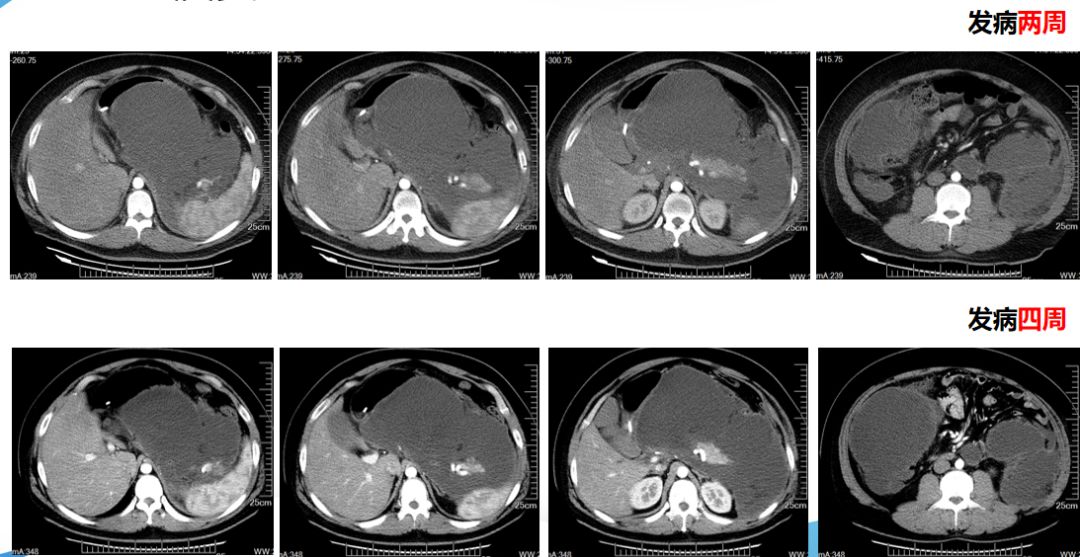

CT演变

血常规:WBC 17.9×10^9/L,N 80.8%;血淀粉酶:691U/L;血甘油三酯:15.7umol/L;腹部CT:急性坏死型胰腺炎。